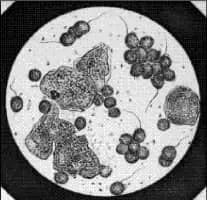

| Known for | Trichomonas vaginalis |

| Leukemia | |

Alfred François Donné was a French bacteriologist and doctor. He was born in Noyon, France, and died in Paris. Donné was the discoverer of Trichomonas vaginalis and leukemia. He was also the inventor of the photomicrography.